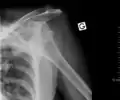

Anterior dislocation of the right shoulder. AP X ray -

Anterior dislocation of the right shoulder. Y view X ray.